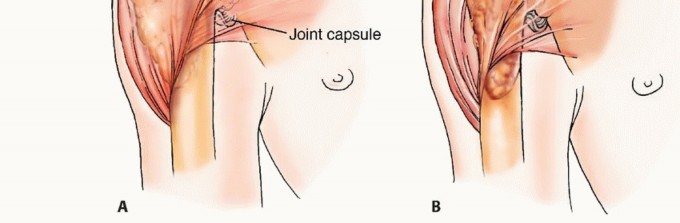

الشكل 1: أ. صورة أشعة سينية تظهر ورمًا نقيليًا في الحُق الأيمن لدى رجل يبلغ من العمر 72 عامًا ولديه تاريخ معروف بسرطان الغدة الدرقية. ب. يظهر التصوير المقطعي المحوسب (CT) تدميرًا واسعًا للعظام وامتدادًا للأنسجة الرخوة. محاولة الاستئصال بناءً على النتائج الشعاعية وحدها قد تؤدي إلى استئصال جزئي للآفة ونزيف محتمل بسبب الأوعية الدموية الكثيفة لهذا الورم. بالنظر إلى هذه النتائج الشعاعية، خضع هذا المريض لانسداد وعائي قبل الجراحة مما قلل من فقدان الدم أثناء الجراحة وسمح باستئصال ناجح.